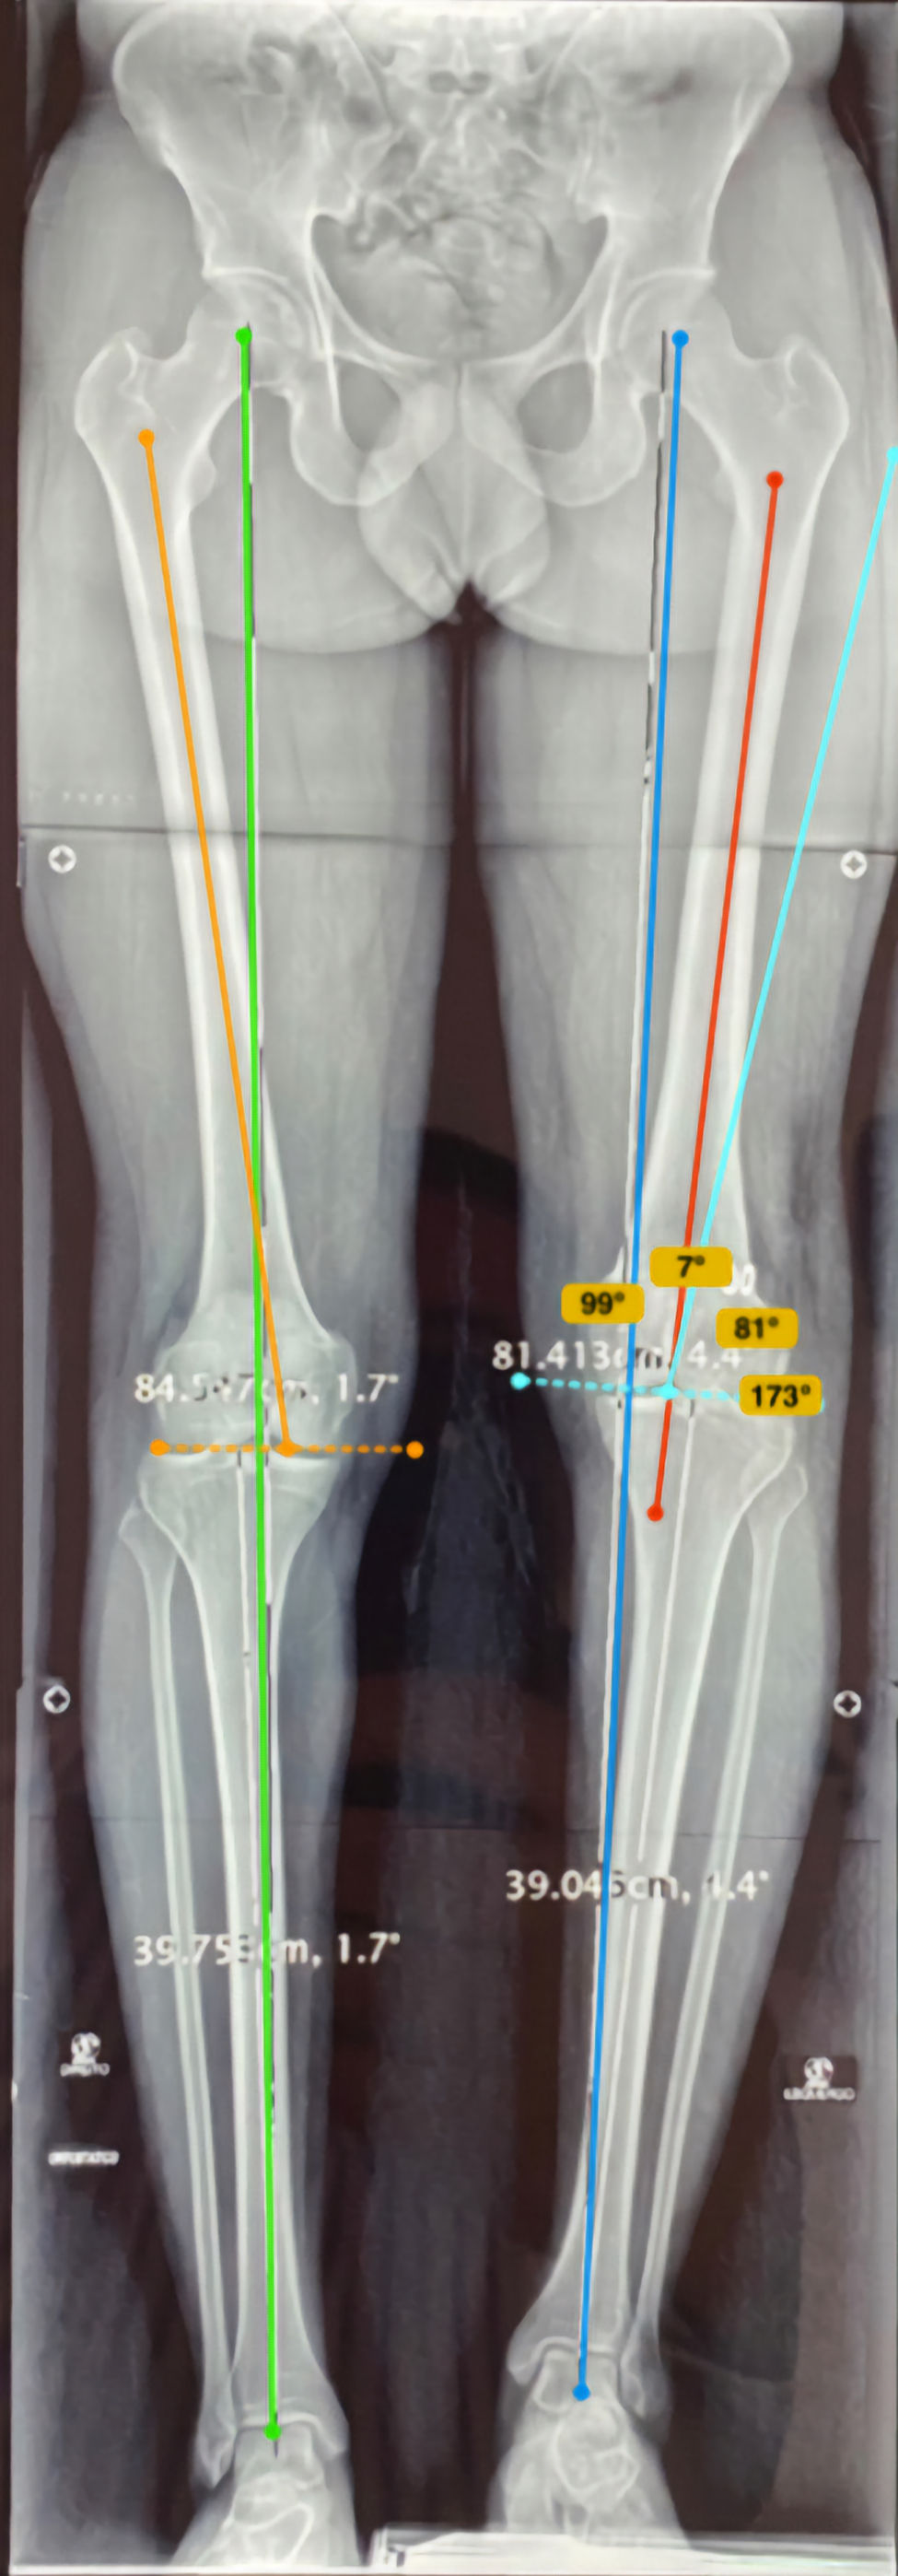

Deformidades crônicas combinam desvios multiplanares, encurtamento, rotação e rigidez articular. O tratamento começa com mapeamento 3D, estudo de eixo mecânico e avaliação de partes moles, nervos e vasos. Empregam-se osteotomias multiplanares, correção gradual com fixadores externos convencionais circulares, fixadores externos monolaterais e fixadores modernos auxiliados por softwares dedicados para ajustes milimétricos, ou correção aguda com placas/hastes quando as partes moles permitem. Enxertos estruturais ou substitutos bioativos auxiliam em perdas ósseas. Em casos com rigidez, liberações capsulares e alongamento muscular são associados. O foco é recuperar alinhamento, função e descarga indolor, com reabilitação intensiva e controle radiográfico seriado.

Deformidades pós-traumáticas

Deformidades pós-traumáticas decorrem de consolidação viciosa, perda óssea, lesões ligamentares e assimetrias residuais. O tratamento inicia com análise clínica e radiográfica tridimensional, avaliação de eixo mecânico, rotação e comprimento, além do estado das partes moles. As opções incluem osteotomias corretivas percutâneas ou abertas, estabilização com fixador externo circular (método de Ilizarov) ou placas/hastes intramedulares, eventualmente associadas a enxertia óssea ou substitutos. Navegação por planejamento digital e guias impressos em 3D aumentam precisão. Reabilitação precoce e ajustes graduais permitem corrigir angulação, rotação e encurtamento com segurança funcional.